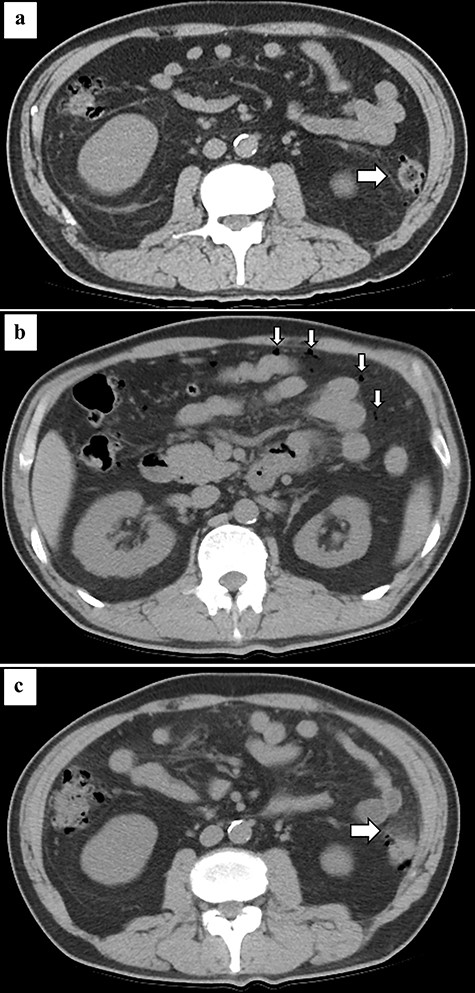

Abdominal CT at the onset of COVID-19 showing diverticulum of the descending colon (arrow) (a). Abdominal CT at the onset of pan-peritonitis showing free air in the abdominal cavity (arrow) (b) and increased fat density surrounding the descending colon (arrow) (c).

Although acute pan-peritonitis due to diverticulum perforation is a common disease, the association between COVID-19 and this disease is unclear. In this case, the descending colonic diverticulum was present at the time of onset of COVID-19 (Fig. 2a), so COVID-19 did not affect diverticulum formation. However, COVID-19 has been shown to cause gastrointestinal symptoms, such as vomiting, diarrhea or abdominal pain during the early phases of the disease. Intestinal dysfunction induces changes in intestinal microbes [2]. These changes can cause diverticulitis. In the present case, diverticulitis developed more than half a year after recovery from COVID-19, so the direct association with COVID-19 might be low.